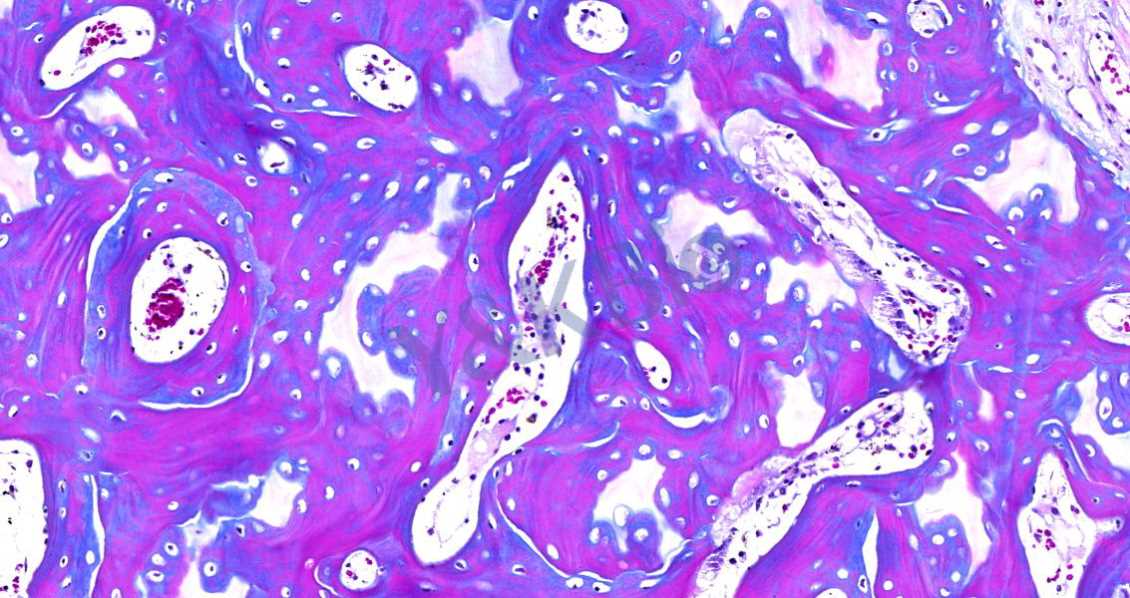

Masson染色的颜色对比鲜明,可见明显的胶原纤维网(云南苯胺蓝染色则为蓝色,甲基绿则为绿色),能较好地反映纤维组织的形态。其中,蓝色表示新形成的骨,红色表示成熟的骨组织。

3.番红O-固绿染色

番红O-固绿染色可直观反映关节软骨、软骨下的骨组织结构,嗜碱性的软骨与碱性染料番红 O 结合呈现红色,嗜酸性的骨和酸性染料固绿结合而成蓝色,在关节软骨及软骨下骨的形态学研究中受到了欢迎。